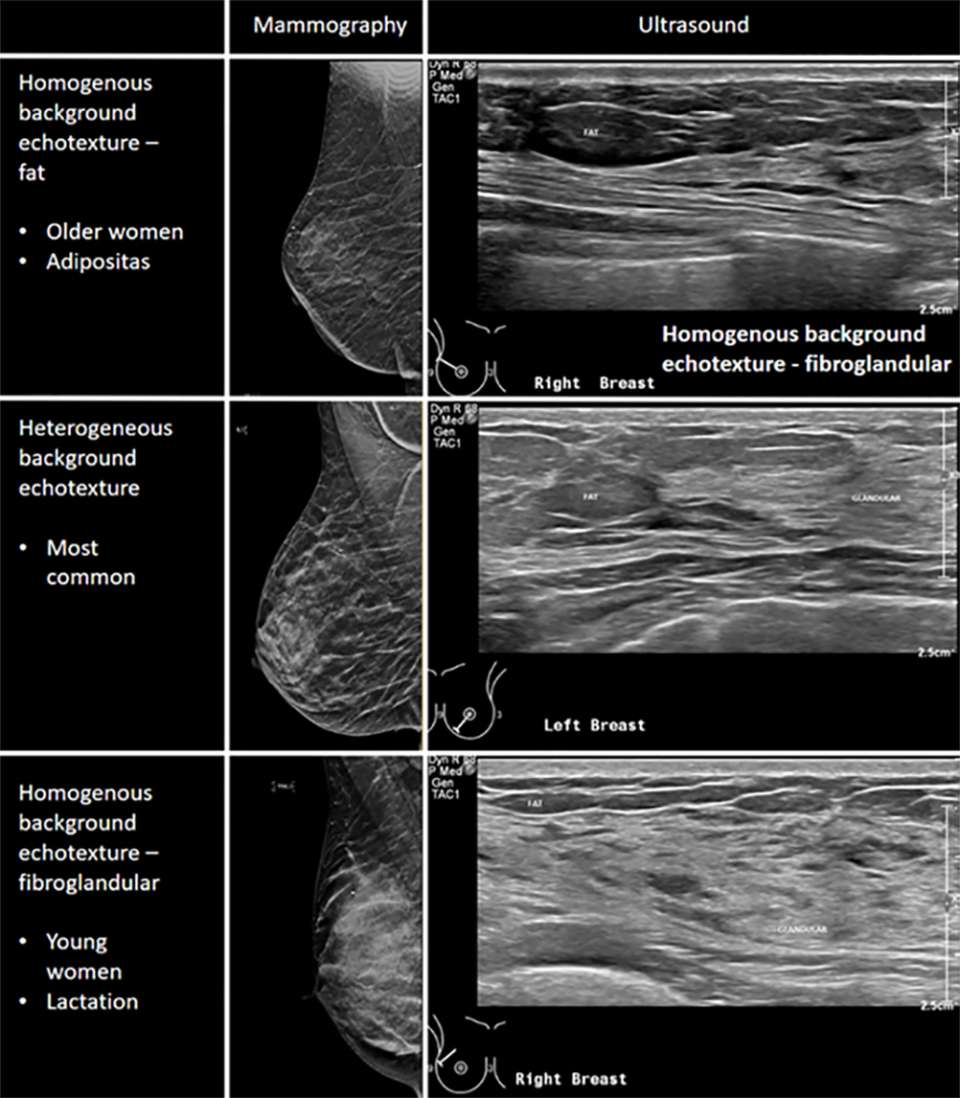

The breast is comprised of a mixture of fatty and fibroglandular tissue. This glandular tissue may be heterogeneously spread throughout the breast, usually more prominent within the upper outer quadrant and centrally in the breast. Glandular tissue can be affected by hormonal fluctuations, for example during the menstrual cycle, pregnancy, or lactation. Additional factors such as medications and age will affect the density of the breast tissue. Based on the Breast Imaging Reporting & Data System (BI-RADS), the lexicon to describe breast tissue composition include homogenous background echotexture – fat, homogenous background echotexture – fibroglandular, heterogeneous background echotexture.

Medical diagram comparing mammography and ultrasound images of breast tissue, illustrating homogeneous fat, heterogeneous, and fibroglandular patterns.

Breast Tissue Composition